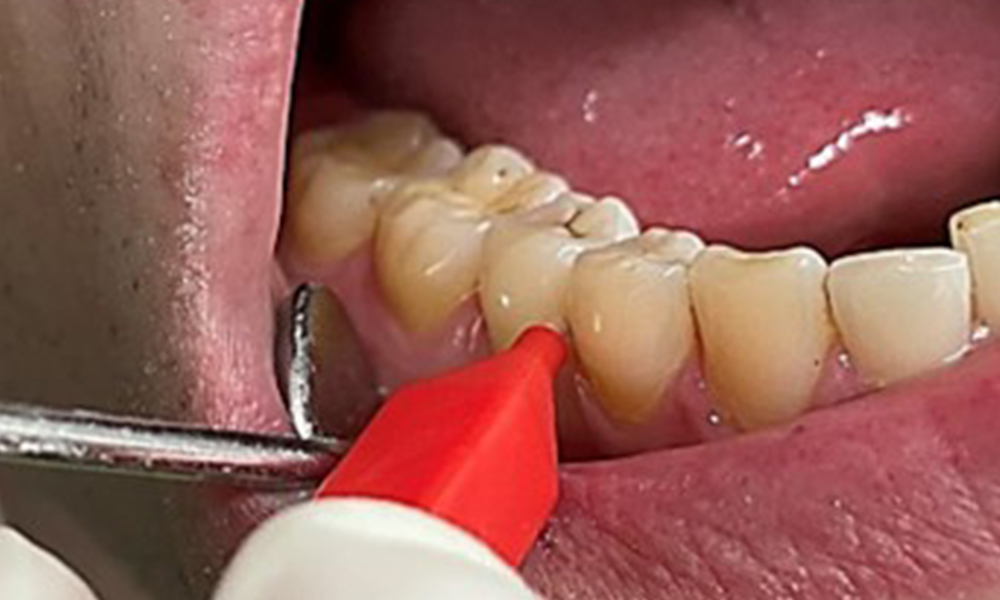

Close-up view of teeth

Fig. 5: Close-up view of teeth 45 to 47. The green arrows show dental attrition and erosions of the buccal cusps with partial enamel loss, © Dr R. Krapf

The patient has full dentition with a total of 28 teeth. There were noteworthy erosions and attritions. (Fig. 4, Fig. 5). Due to bruxism, the patient has been wearing a splint with an adjusted bite block at night for many years. The erosions were caused by long-term consumption of isotonic beverages. No periodontal bone loss or active caries were observed.

Full complement of adult teeth with no caries or radiologically recognizable bone loss was observed (Fig. 6). Radiological enamel and cusp loss were particularly evident on 36 and 37.